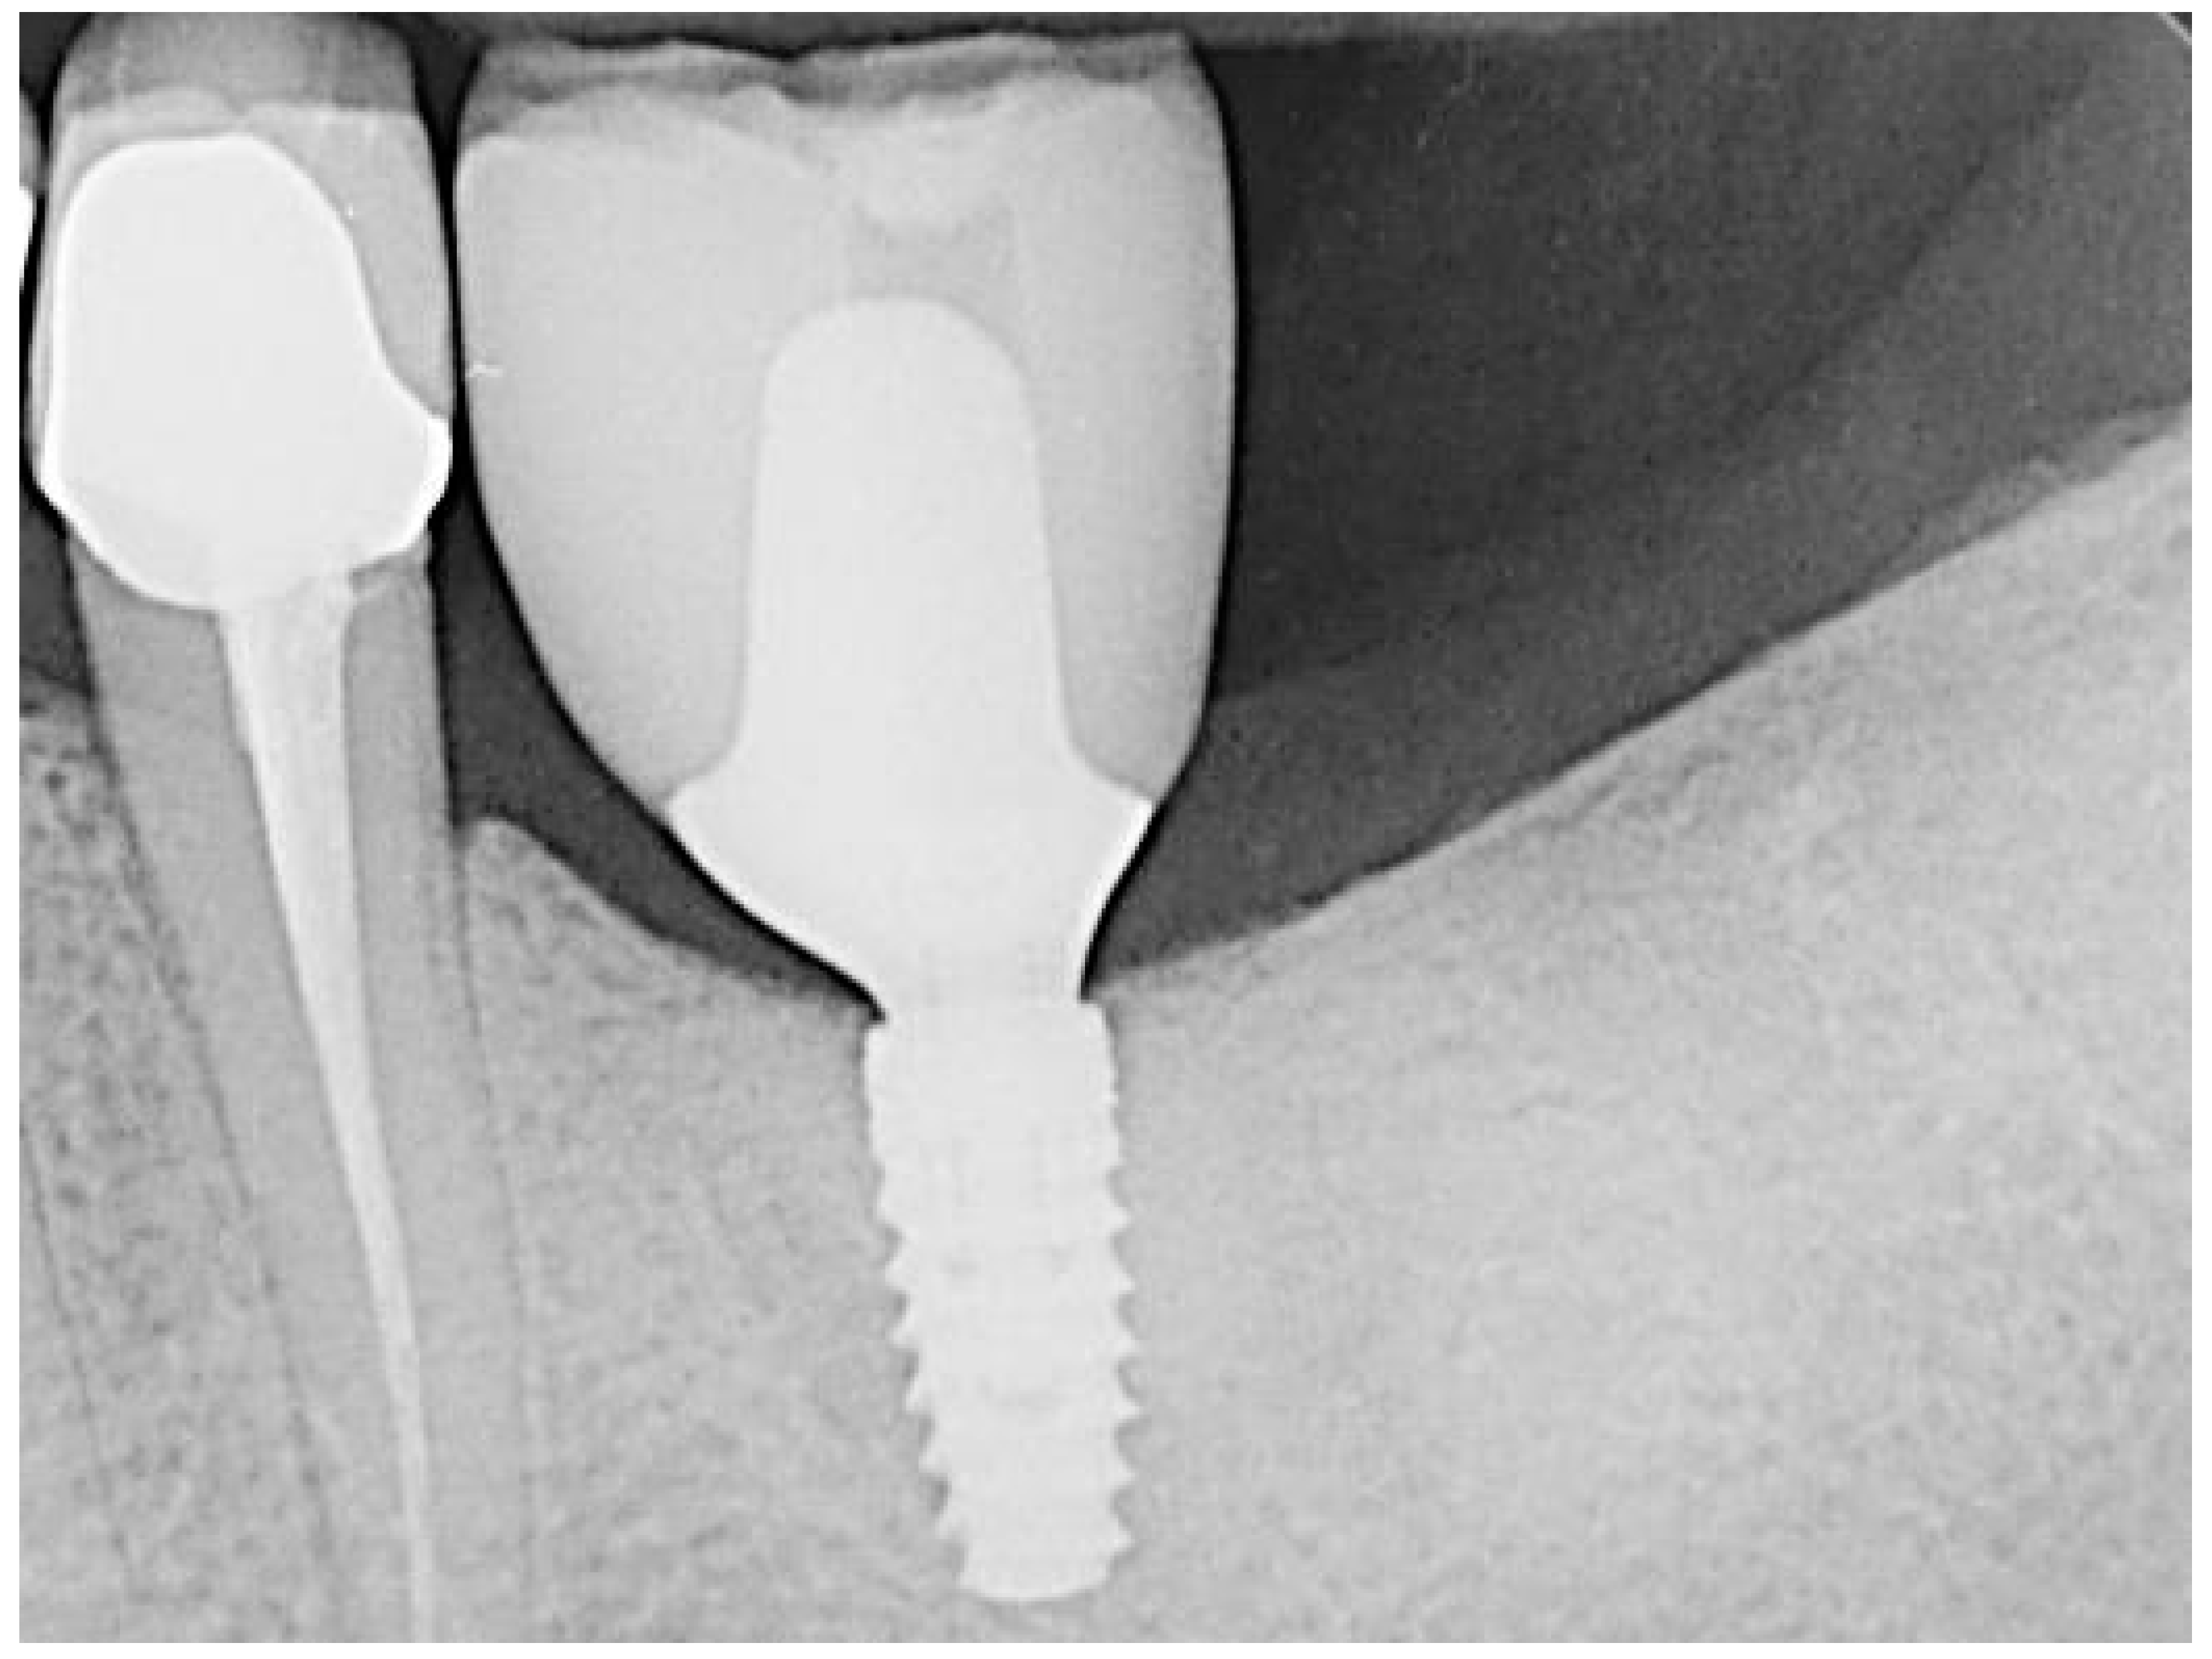

Figure 6.

Regio 36 after implantation.

The teeth required extraction for various reasons, but a consistent ARP protocol was utilized for all the sockets. Multirooted teeth were sectioned with a small rotating Lindemann bur (H162AZ, Komet, Gebr. Brasseler GmbH; Lemgo, Germany), and the root fragments were carefully and atraumatically elevated and extracted using matching periotomes (PT Periotomes, Hu Friedy, Chicago, IL, USA) under local anesthesia (Ultracain DS forte, Sanofi, Paris, France) to minimize the risk of iatrogenic damage to the alveolus. The remaining granulation tissue was removed using degranulation burs (EthOss, Ethoss Regeneration Ltd., Silsden, UK) (Figure 1) to prevent any adverse effects on alveolar healing due to soft tissue remnants. The biomaterials used included a native bovine, cross-linked collagen membrane (xCM) composed primarily of type 1 collagen fibers from the Achilles tendon (Memlok RCM, BioHorizons, Birmingham, AL, USA) and a deproteinized bovine bone material combined with species-specific collagen (C-DBBM) in the form of moldable bone blocks (MinerOss X Collagen, BioHorizons, Birmingham, AL, USA) (Figure 2), in accordance with the EFP recommendations at that time [18] and rehydrated according to the manufacturer’s instructions. The bone substitute material is predominantly composed of 95% anorganic cancellous bovine mineral granules and 5% bovine collagen. It undergoes terminal sterilization and exhibits a particle size ranging from 250 to 1000 µm. The bony edges of the sockets were exposed using a periosteal elevator. The xCM was carefully adapted to the sockets, ensuring an overlap of 2 mm to prevent soft tissue ingrowth. Subsequently, the vestibular part of the membrane was repositioned for direct access to the sockets. The C-DBBM blocks were cut to the appropriate size with a 15C scalpel. After placement into the sockets, moderate compression was applied with a bone compactor, avoiding overfilling (Figure 3). The membrane was double-folded on the oral aspect and repositioned over the bony edges of the sockets. The membranes were left exposed to the oral cavity. Complete wound closure, which would require extensive mobilization and potentially shift the mucogingival border, was not attempted. A crisscross suture using a Glycolon 6-0 resorbable thread (Resorba Medical GmbH, Nurnberg, Germany) provided temporary stability and slight wound margin adaptation. If necessary, papillae adaptation was performed using the same suture material with single interrupted sutures (Figure 4). A postoperative dental X-ray was taken to document the completion of the ARP procedure (Figure 5). The provisional treatment involved clip-anchored removable dental prostheses to prevent elongation, tooth tilting, or psychosocial issues due to tooth gaps, ensuring proper food intake. The patient was given non-steroidal anti-inflammatory drugs for pain relief (600 mg Ibuprofen, Ibuflam, Zentiva, Pharma GmbH, Berlin, Germany). The postoperative regimen included avoiding mechanical plaque control in the treated area for one week and using an alcohol-free chlorhexidine mouth rinse 0.2% (Chlorhexamed, GlaxoSmithKline Consumer Healthcare GmbH & Co. KG, Munich, Germany) twice daily. The sutures were removed after four weeks. A healing period of at least 19 weeks was planned to ensure a stable implant site. Presurgical assessment of the alveolar ridge was performed using cone beam computed tomography (Orthophos XG 3D, Dentsply Sirona, York, PA, USA) to enable flapless surgery by fabricating a static computer-aided implant surgery drilling guide. After administering local anesthesia (Ultracain DS forte, Sanofi, Paris, France), the implant site was prepared with a mid-crestal incision to maintain sufficient keratinized tissues. The implant site was prepared with a trephine bur (Trephine Ejection Kit, Hager & Meisinger GmbH, Neuss, Germany), the intended implant was placed, and a postoperative radiographic examination was performed (Figure 6). After carefully removing the bone core from the trephine, it was stored in a buffered 10% formalin solution. The implants healed submerged. The sutures were removed after ten days. The implants were uncovered after four months, followed by impression-taking after another four weeks and the final placement of screw-retained single-tooth restorations, consisting of custom titanium abutments with lithium disilicate crowns. A dental X-ray was taken at the conclusion of the prosthetic phase (Figure 7).